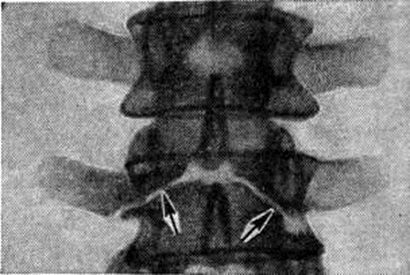

Чаще встречаются дефекты в дугах позвонков, особенно нижних поясничных и крестцовых. Наиболее типично незаращение дуги по средней линии с расщеплением и недоразвитием, а иногда и отсутствием остистого отростка. Эта локализация Спина бифида легко выявляется на рентгенограмме в прямой проекции (рисунок 4). Реже расщелина локализуется в дуге между суставными отростками с одной или с обеих сторон — спондилолиз (рисунок 5). Диагностика Спина бифида этой локализации сложна, если она не сочетается со спондилолистезом (смотри полный свод знаний). При подозрении на спондилолиз обязательна рентгенография в двух проекциях, а при недостаточной информативности рентгенограмм необходимо томографическое исследование в боковой проекции (смотри полный свод знаний: Томография).